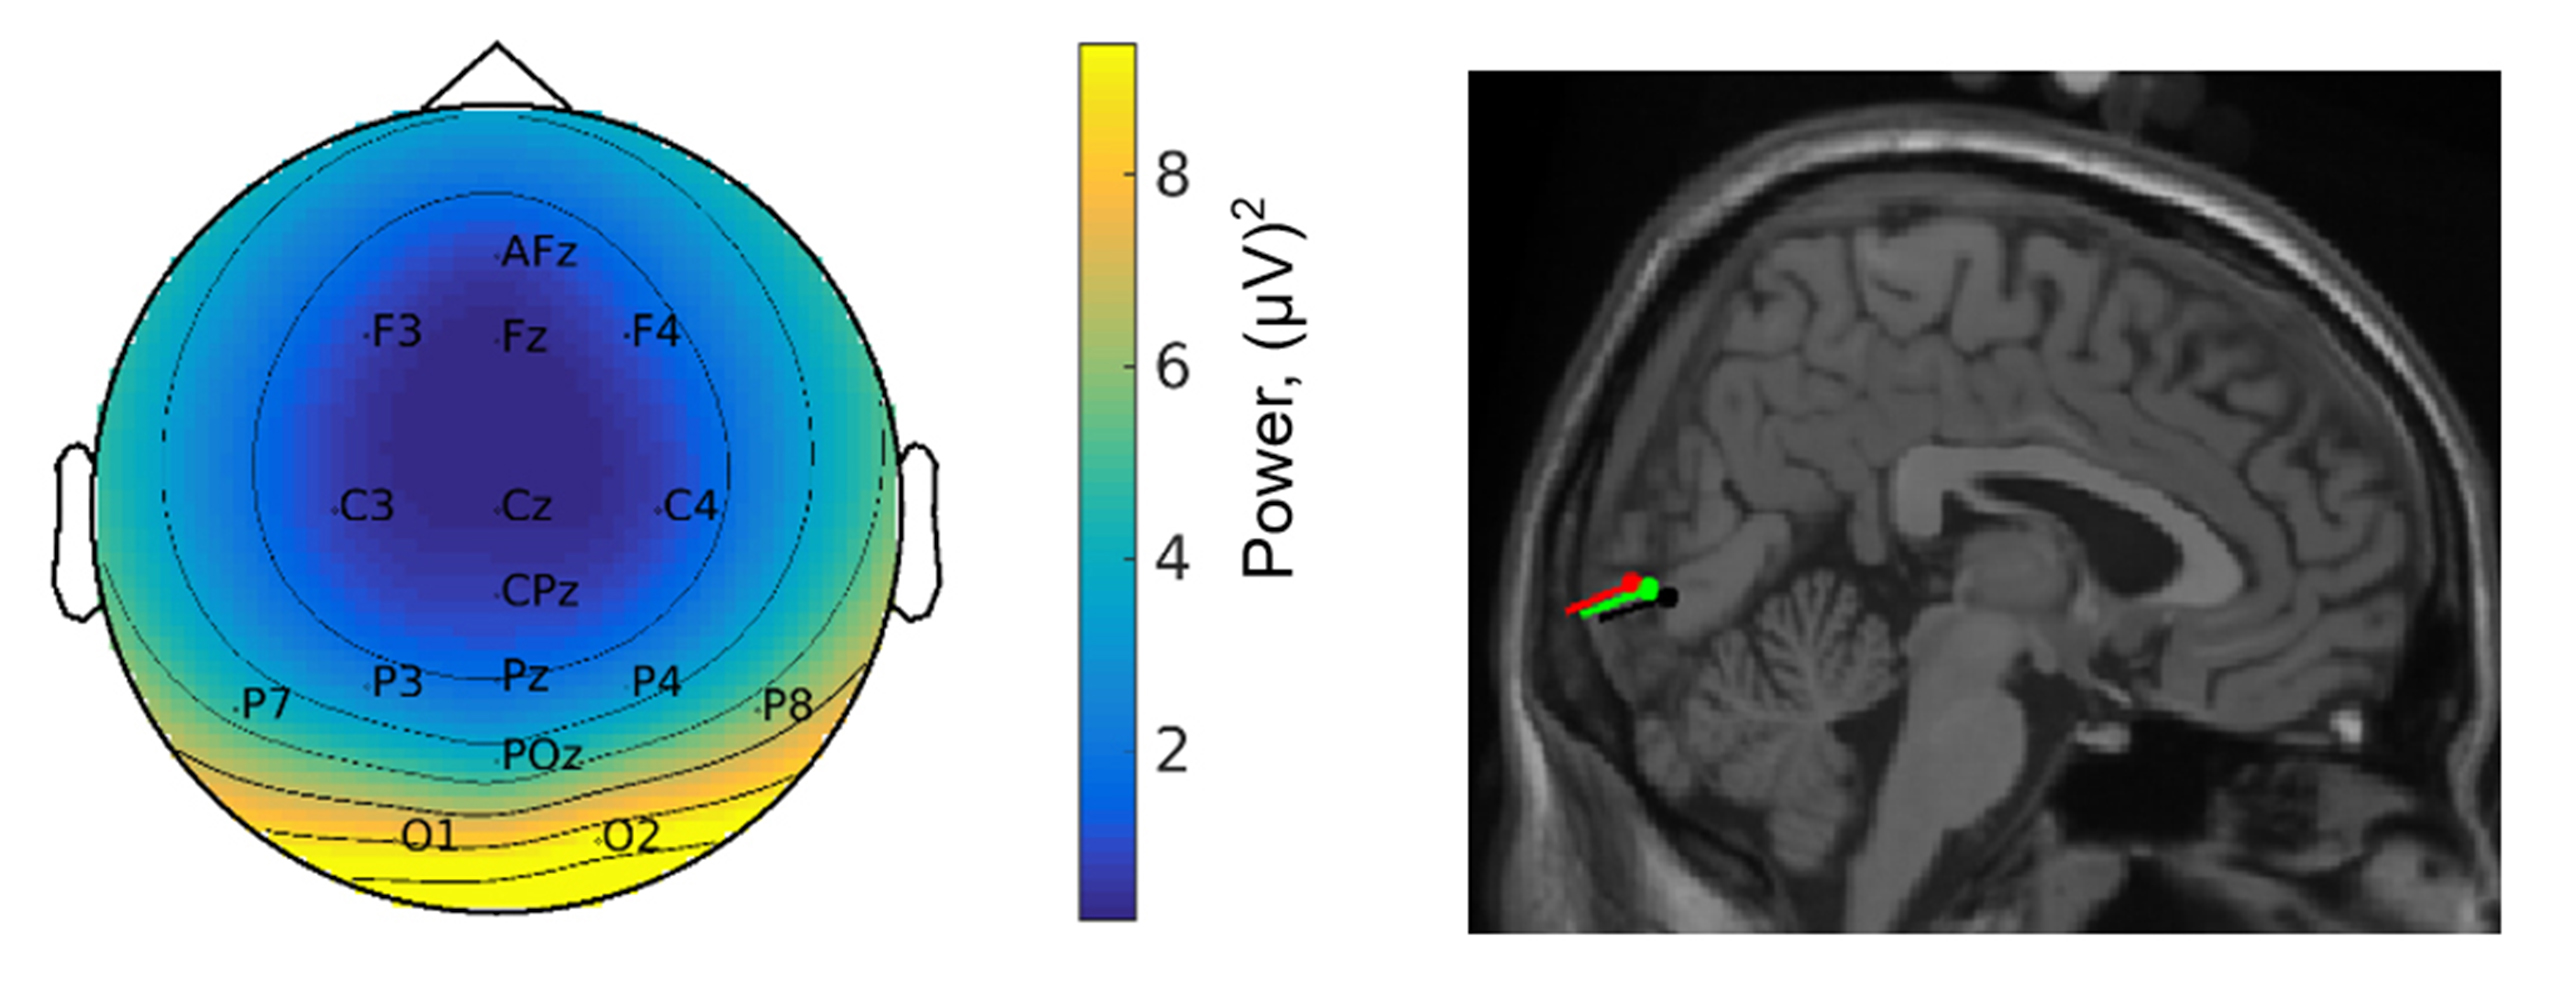

Topographie der EEG-Antwort (l.) und ihre Lokalisation im Gehirn (r.) zeigen visuelle Verarbeitungsprozesse bei den Bewegungsbedingungen langsames und normales Gehen – grün und rot; Stehen – schwarz.

Quelle: (Bild: Barbara Händel / Universität Würzburg) (idw)